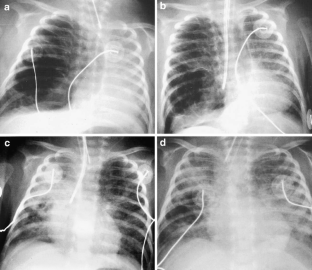

Fig. 2